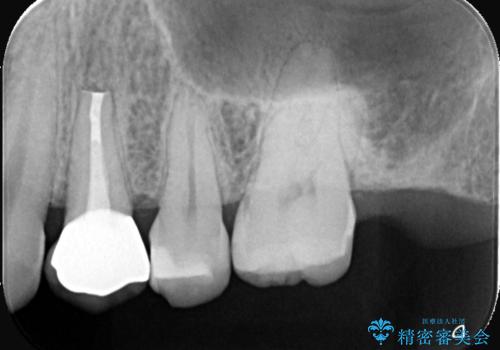

結果、根管内にはイスムスにデブリが多く見られたものの破折線は確認できませんでした。再根管治療後、症状の経過を3ヶ月ほど確認しましたが打診、違和感が消失しておらず、外科的歯内療法を行うこととなりました。

結果、症状改善し治癒良好と判断できます。